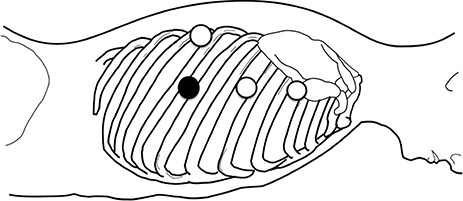

An 83-year-old-woman presented with a subcarinal mass detected by a precise examination of upper abdominal pain worsening after meals. Magnetic resonance imaging revealed a well-circumscribed cystic mass in the subcarinal area compressing the surrounding organs and suggested a BC as the most likely diagnosis (Fig 1). She had poorly controlled type 2 diabetes mellitus (A1c level 9.1%), hypertension, and also noted worsening paroxysmal atrial fibrillation (CHADS2 score3) and was receiving dabigatran etexilate over the last several months. A surgical resection of the cyst was recommended. With the patient in the prone position, two 5-mm ports in the third and fifth inter costal spaces (ICSs) and a 12-mm port in in the seventh ICS on the mid-axillary line were made, respectively. An additional 5-mm port was inserted into the eighth ICS on the scapular line and used as a camera port (Fig 2). Carbon dioxide (CO2) was insufflated at a pressure of 8–mm Hg and then a tense mass was clearly visualized in the subcarinal area (Fig 3). The cyst wall was found to have strictly adhered to the adjacent organs suggestive of past inflammatory events. Because an attempt to dissect between the cyst and lung resulted in parenchymal injury with alveolar leakage, we considered that the lesion was not amenable to a complete excision. After

The patient position and port insertion sites; three 5-mm ports (open circles) and one 12-mm port (filled circle) were placed.